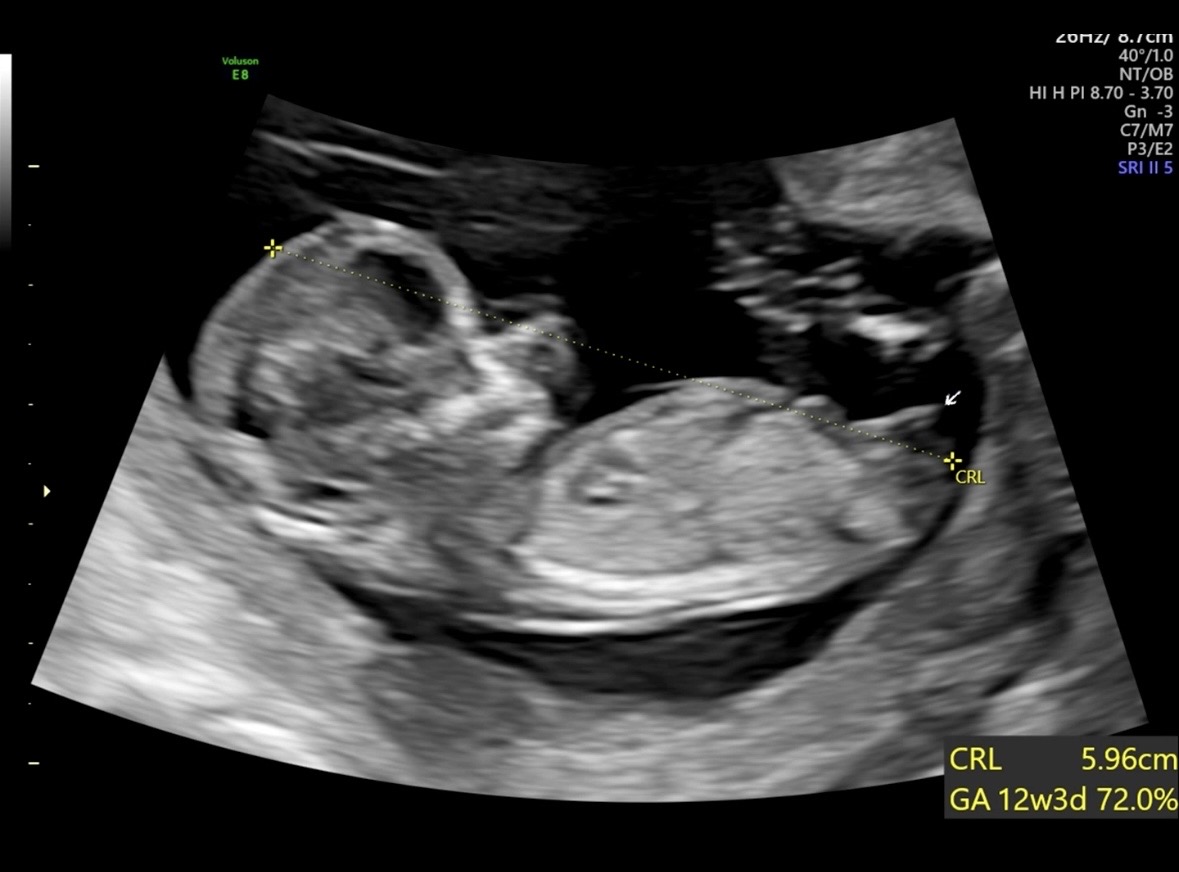

12주차 각도법 부탁드려요!!

베이비빌리랑 각도법 사이트에서는 여아로 나왔는데, 마우스 포인트 부분인 성기가 너무 튀어나온 것 같아서요! 각도법 부탁드립니다 😊